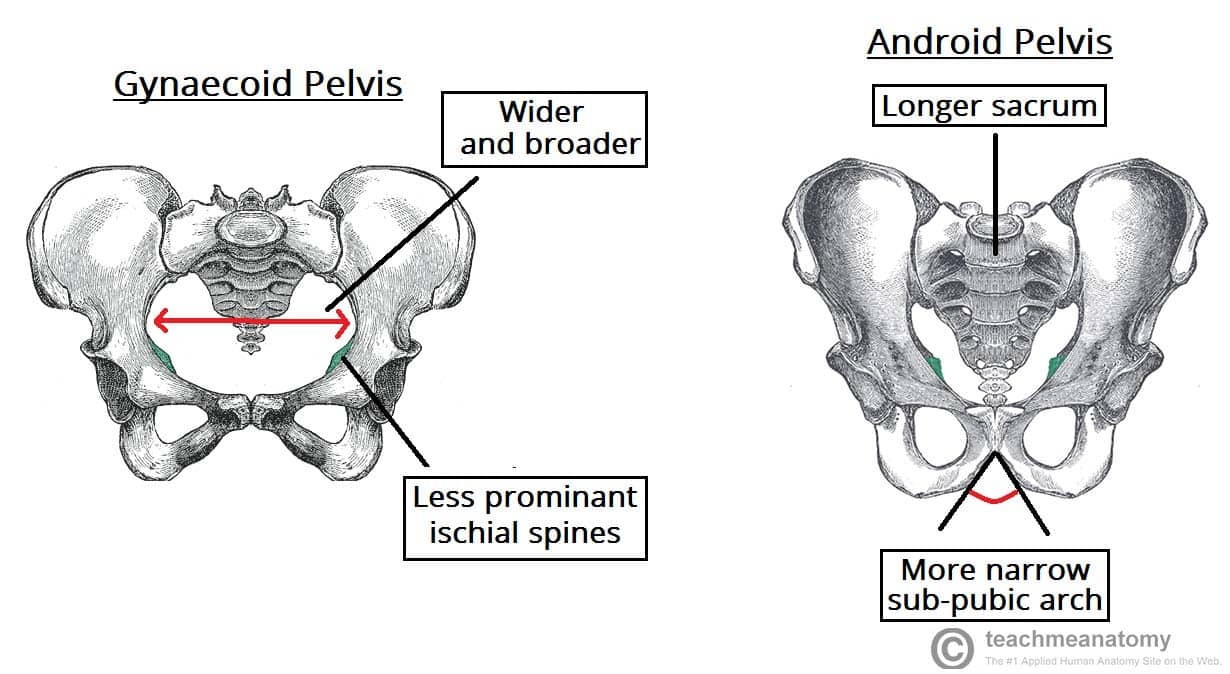

When faced with a challenging clue like “pelvic bones,” it’s essential to think outside the box. Consider related terms such as anatomy, skeletal system, or even medical terminology. Sometimes, the answer lies in a different context than you initially thought.

Another approach is to break down the clue into its individual parts. In this case, “pelvic” refers to the area of the body, while “bones” obviously points to skeletal structures. By dissecting the clue in this manner, you may uncover hidden connections that lead you to the correct answer.

Ilium bone Wikipedia